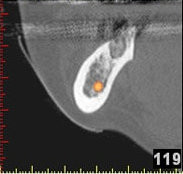

In komplexen Fällen, z. B. der Implantatversorgung eines kompletten Kiefers, oder bei schwierigen Knochensituationen bietet die 3-dimensionale Computerdiagnostik bzw. Planung und Durchführung erhebliche Vorteile und Sicherheit für den Patienten (siehe Bild 1 und 2).

Auf Basis einer computertomografischen (CT-) Kieferaufnahme ist eine dreidimensionale Darstellung der Knochen möglich. Der Zahnarzt kann dann am Computerbildschirm die Knochenqualität (z. B. Knochendichte) beurteilen und die optimale Position der Implantate im Vorfeld planen. Durch Verwendung spezieller Röntgenschablonen lässt sich auch die erwünschte Zahnstellung in die Planung einbeziehen. Die Simulation der OP erlaubt, das zu erwartende Ergebnis mit größtmöglicher Sicherheit vorherzusagen und dem Patienten am Bildschirm zu veranschaulichen.